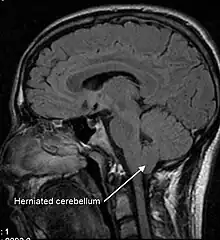

An untreated CSF leak can result in coma or death as late stage findings as the brainstem herniates through the skull base or foramen magnum .[35][33]

Arnold–Chiari malformation is a condition where the cerebellar tonsils have descended, and should be considered in differential diagnosis of sCSFLS.

Low CSF volume can cause the cerebellar tonsil position to descend, which can be mistaken for Chiari malformation; however when the CSF leak is repaired the tonsil position often returns to normal (as seen in upright MRI) in this "pseudo-Chiari" condition.[57] A further, albeit rare, complication of CSF leak is transient quadriplegia due to a sudden and significant loss of CSF. This loss results in hindbrain herniation and causes major compression of the upper cervical spinal cord. The quadriplegia dissipates once the patient lies supine.[58] An extremely rare complication of sCSFL is third nerve palsy, where the ability to move one's eyes becomes difficult and interrupted due to compression of the third cranial nerve.[59]

Lack of CSF pressure and volume can allow the brain to sag and descend through the foramen magnum (large opening) of the occipital bone, at the base of the skull. The lower portion of the brain is believed to stretch or impact one or more cranial nerve complexes, thereby causing a variety of sensory symptoms. Nerves that can be affected and their related symptoms are detailed in the table at right.[21][23][28] A rare form of dementia known as brain sagging dementia may be caused by a sagging brain, a characteristic of intracranial hypotension.[16]

There is disagreement over whether MRI should be the diagnostic tool of choice.[23][31][41] Magnetic resonance imaging is less effective than CT at directly imaging sites of CSF leak. MRI studies may show pachymeningeal enhancement (when the dura mater looks thick and inflamed), sagging of the brain, pituitary enlargement, subdural hygromas, engorgement of cerebral venous sinuses, and other abnormalities.[31] For 20% of patients, MRIs present as completely normal.[31] MRIs performed with the patient seated upright (vs. laying supine) are not better for diagnosing CSF leaks,[67] but are more than twice as effective at diagnosing cerebellar tonsillar ectopia, also known as Chiari malformation.[68] Cerebellar tonsillar ectopia shares many of the same symptoms as CSF leak,[57] but originates either congenitally or from trauma, including whiplash strain to the dura.[68]